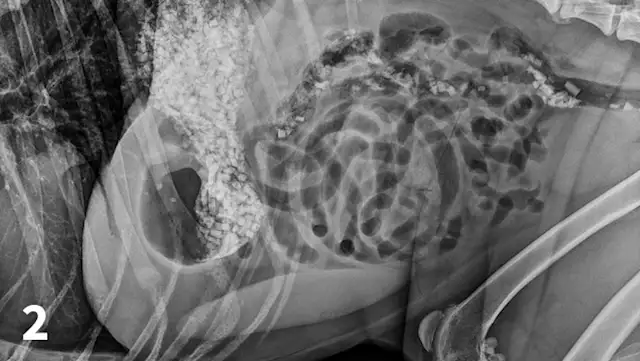

CBC reveals a leukocytosis (19.34 103/L; range, 5.10-14.00) characterized by a lymphocytosis (5.5 103/L; range, 1.4-4.6) and a mature neutrophilia (13.10 103/L; range, 2.65-9.80) with a mild thrombocytopenia (171 103/L; range, 147-243). A pancreatic-specific lipase is elevated (580 g/L; range, 0-200 g/L) and consistent with pancreatitis. Abdominal radiographs (Figures 1-3; See below) reveal a moderately distended stomach that contains a large number of irregularly shaped mineral opacities. Additional mineral opacities are present in multiple small intestinal segments as well as the colon. There is also a mild decrease in serosal detail in the mid-abdominal region.

A right lateral abdominal radiograph taken approximately 24 hours after glass ingestion. Multiple, irregularly shaped mineral opacities are present within the stomach, small intestine, and colon.